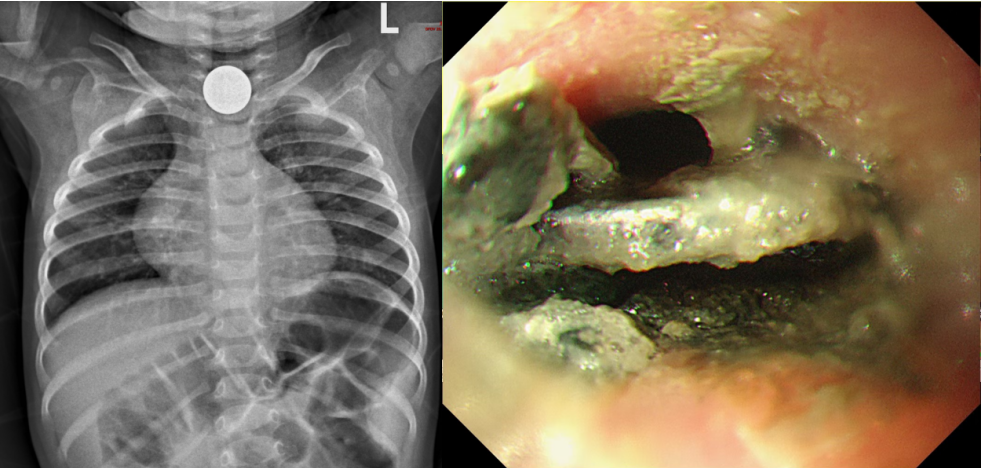

29 例纽扣电池误食患儿中,1 例因食管气管瘘抢救无效导致家属放弃治疗,电池的腐蚀性可在短短两小时内造成严重的组织损伤 [2];